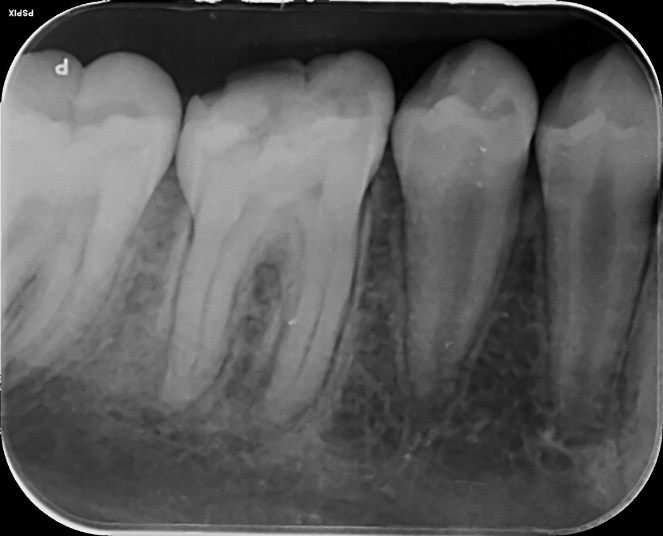

Lower Molar and premolar Primary root canal treatment